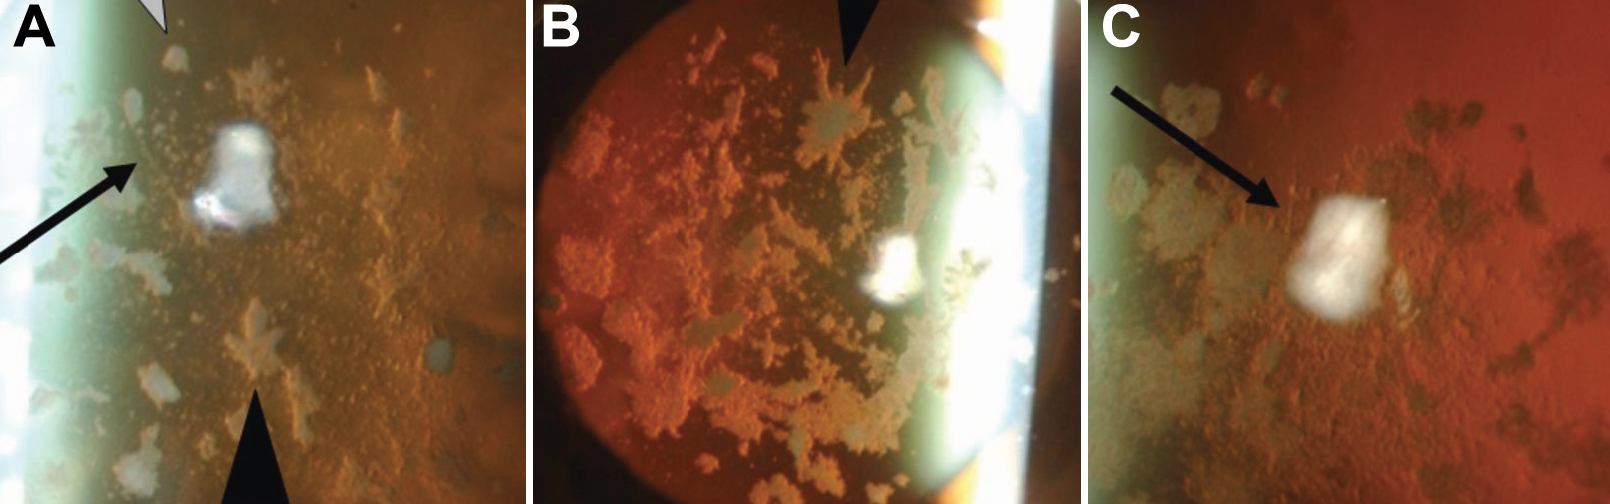

Figure 3 of Yamada, Mol Vis 2009; 15:974-979.

Figure 3. Lattice lines in patient's cornea. The lattice lines referred to in Figure 2 are better visualized in the higher magnifications of Figure 2C, Figure 2F, and Figure 2I (Figure 3A-C, respectively). The lattice lines are easily seen in A and C (black arrows), but not in B.